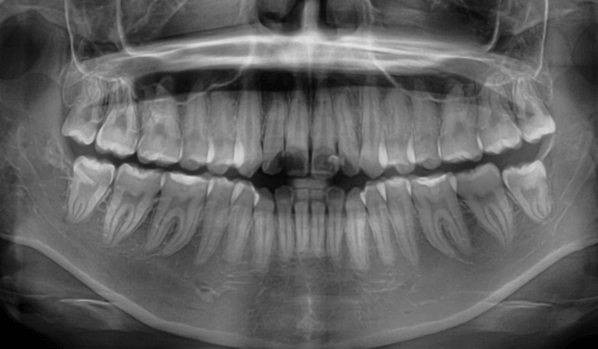

次に、X線撮影、口腔内撮影、お顔の撮影などを実施します。これらは矯正治療を行うのに重要な検査となります。

小児矯正の場合、これらの検査に加え、手根骨とよばれる成長の指標となる骨の撮影を必要に応じて行います。